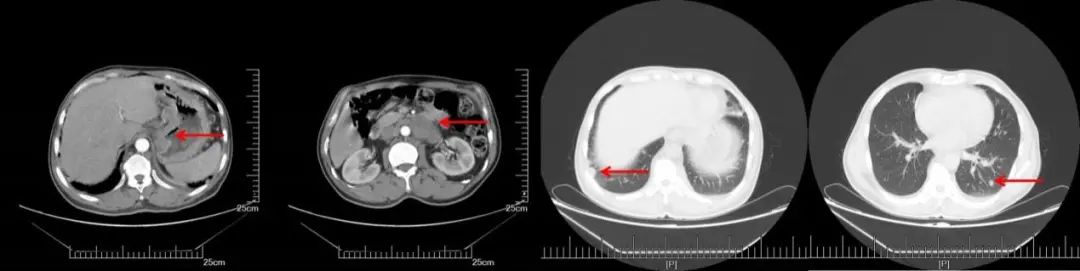

CT(2016-8-22):1、胃体癌并肝胃间、腹膜后多发淋巴结转移,强化均匀,最大横径约17mm。2、双侧膈肌脚后及纵隔内多发淋巴结,部分增大,最大横径约14mm。3、双肺多发小结节,考虑转移。

CT(2016-8-22):胃体小弯侧增厚,肝胃间、腹膜后多发淋巴结转移,双肺多发转移。

2016.8~2016.10给予SOX方案化疗2个周期(奥沙利铂:200mg d1,替吉奥:60mg po Bid,q21d),疗效评价:接近PR。

A:CT增强(2016.08.22): 胃体小弯侧增厚,肝胃间、腹膜后多发淋巴结转移,双肺多发转移。B:2周期化疗后CT增强(2016.10.19):胃壁增厚减轻,淋巴结明显缩小,双肺多发转移灶几乎消失

2、第2次MDT:该患者两个周期的一线治疗方案,双肺转移灶基本完全消失,腹腔淋巴结较前缩小,疗效评估接近PR,但目前仍然无根治的手术机会,建议继续SOX方案化疗,同时,仍要建议患者行HER2基因检测。但患者提出既往曾出现过呕血病史,惧怕再次出现呕血状况发生,遂强烈要求行手术治疗。